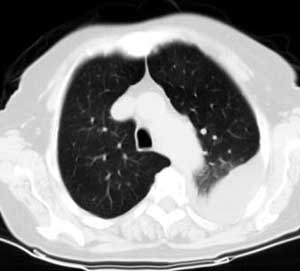

标题: CT0563:病历讨论,胸膜间皮瘤?

测ct值3-6hu,

既然ct值是3-6hu,还不如考虑包裹性积液。

请上传纵隔窗。目前还是支技包裹性积液(明显梭形),即使是间皮瘤并积液也少梭形的。

从图片看,包裹性积液好象更合理,梭形,ct值3-5hu(在哪看到的?);胸膜间皮瘤如此规则,不多见。

左侧背部胸膜肥厚,伴包裹性积液,不考虑间皮瘤.

同意以上各位的高见,首先考虑包裹性积液,1.胸膜间皮瘤积液量一般较大,以游离性积液更为常见,2.可以看到增厚的胸膜结节